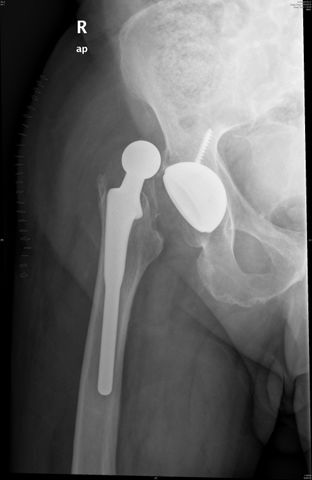

Fractura cuello fémur. Prótesis completa.

Fractura de fémur, prótesis parcial de cadera